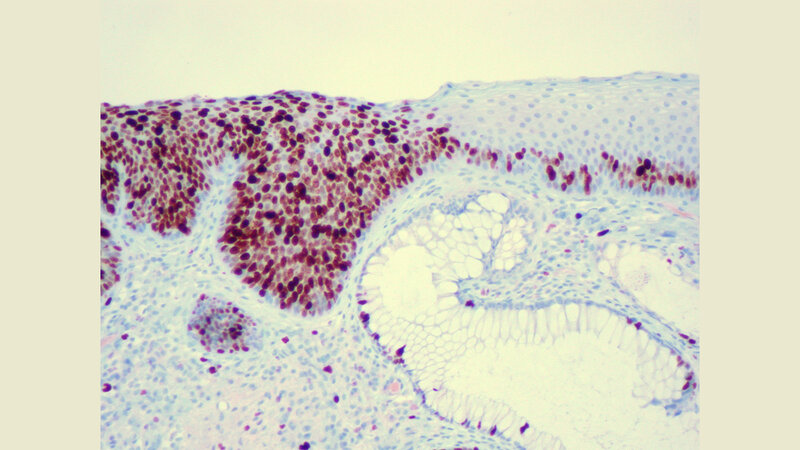

Tumoren im Analkanal unterscheiden sich feingeweblich von Tumoren des übrigen Enddarmes. Während im Analkanal Plattenepithelkarzinome vorliegen, treten im übrigen Dickdarm Adenokarzinome auf. Bis zu den 1980er-Jahren bestand die Therapie des Analkarzinoms in einer Operation, bei der meistens der gesamte Analkanal einschließlich des Schließmuskels entfernt und dementsprechend ein permanenter künstlicher Darmausgang angelegt werden musste [4]. Seitdem hat sich die Therapie laut DEGRO drastisch gewandelt, der Einsatz der lokalen Strahlenchemotherapie mache inzwischen in den allermeisten Fällen eine Operation unnötig. Da Plattenepithelkarzinome des Analkanals besser auf eine Strahlenchemotherapie ansprechen als Adenokarzinome des Darms, stelle sie heute die Therapie der Wahl dar und ermögliche oft eine funktionserhaltende Behandlung.